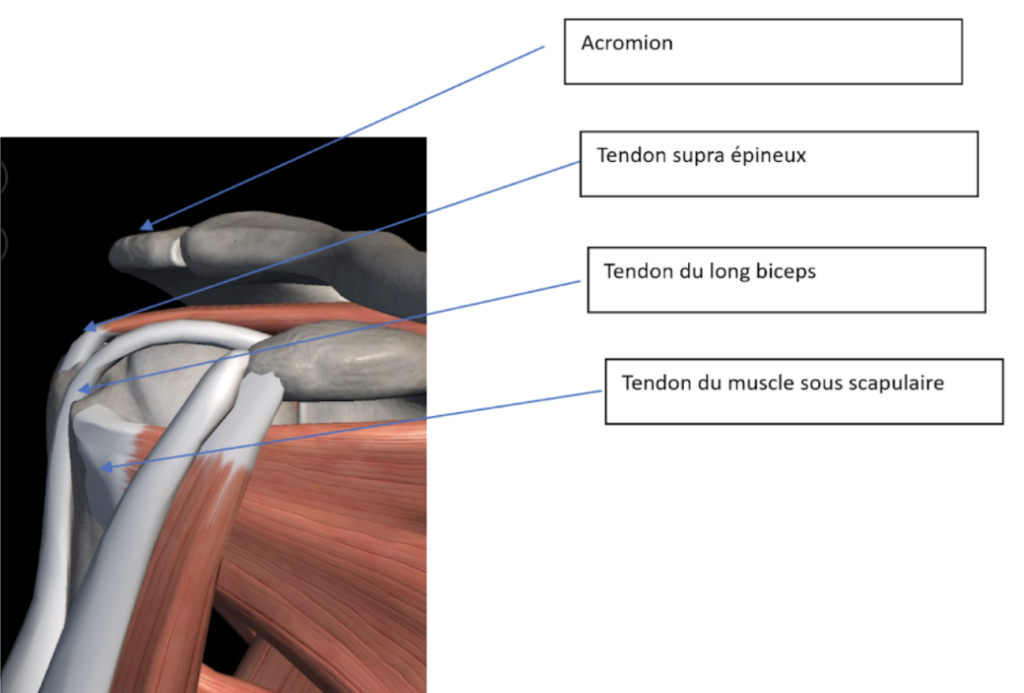

La coiffe des rotateurs est un groupe de quatre muscles et tendons qui viennent coiffer la tête de l’humérus, afin de donner à l’épaule de la force pour lever le bras et une meilleure stabilité.

Ces tendons sont protégés par des bourses, sortes de poches, contenant plus ou moins de liquide, permettant de faire glisser les différentes structures entre elles, sans accrochage. La bourse sous acromiale est une de ces poches, située entre la coiffe et l’acromion, qui n’est autre que l’os faisant le galbe de l’épaulette (partie sur laquelle nous mettons les bretelles du soutien-gorge par exemple).

Vue postérieure de la coiffe des rotateurs

Vue antérieure de la coiffe des rotateurs

La rupture de la coiffe des rotateurs se réfère à une lésion touchant un ou plusieurs tendons au niveau de l’épaule. La coiffe des rotateurs est constituée de quatre tendons – le petit rond, le sous-épineux, le sus-épineux et le sous-scapulaire – qui recouvrent la tête de l’os du bras (humérus). Ces tendons jouent un rôle crucial dans la mobilité de l’épaule, notamment dans les mouvements d’élévation et de rotation.